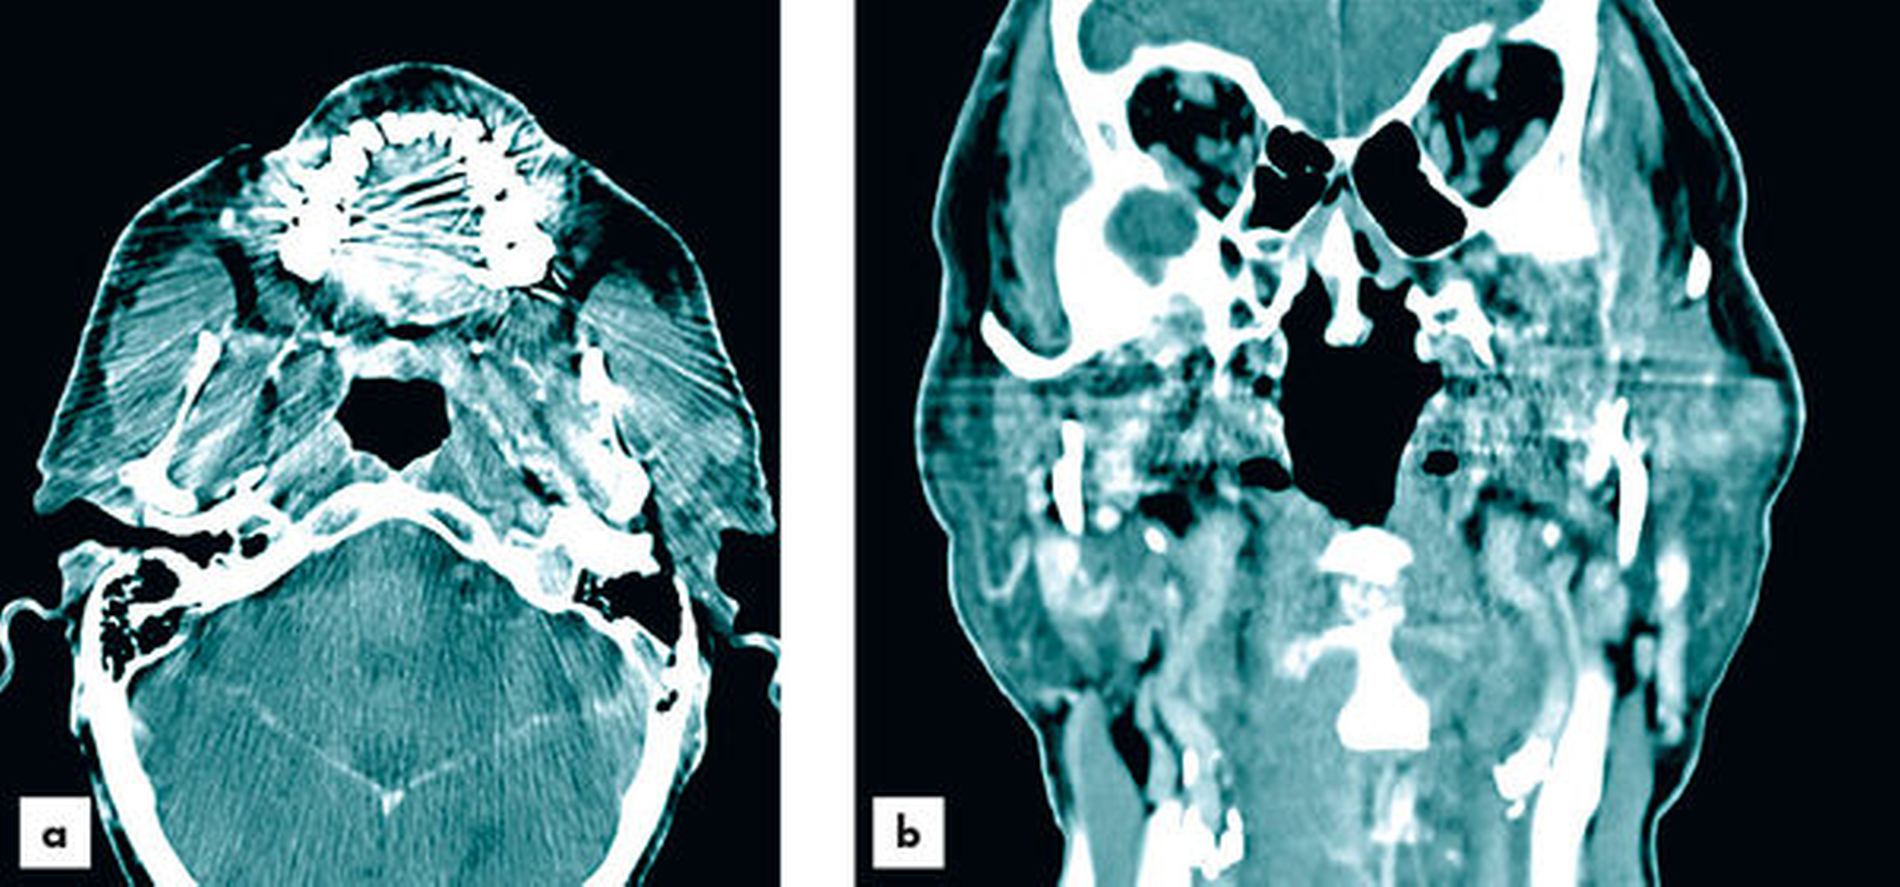

Zur aktualisierten Diagnostik wurde ein Kontrastmittel-CT (Abbildungen 2 und 3) durchgeführt, bei dem neben der bereits bekannten Raumforderung der Glandula parotis links ebenfalls Raumforderungen in der Glandula submandibularis und der Glandula sublingualis rechts festgestellt wurden. Das CT wies im Bereich der Parotis multifokale hypodense, zystische Komponenten sowie dünne Wände und Septen auf. Die Ausdehnung der Neoplasie erstreckte sich bis in die tieferen Anteile des Drüsenparenchyms. Verkalkungen waren nicht nachweisbar und die Kontrastmittelaufnahme erwies sich als moderat. Die Glandula submandibularis und die Glandula sublingualis rechts imponierten ebenfalls durch unklare Kontrastmittelaufnahme. Bildmorphologisch bestand kein Hinweis auf Malignität. Nebenbefundlich lag bildmorphologisch eine chronische Sinusitis maxillaris mit dentogenem Fokus 26 und 27 vor. Die radiologische Verdachtsdiagnose lautete: Verdacht auf bifokalen Warthin-Tumor und bildmorphologisch nicht eindeutig einzuordnende, aber verdächtige Veränderungen der Glandula submandibularis und der Glandula sublingualis rechts.

Bildmorphologisch sind Warthin-Tumore von einer Kapsel umschlossen und erreichen durchschnittlich eine Größe von 3 bis 4 cm [Donath und Ussmüller, 2020]. Im CT zeigen die Raumforderungen hypodense Dichtewerte mit anteilig zystischen Veränderungen [Kloth et al., 2015]. Es treten dünne Wände und Septen auf, wobei es nicht zu Verkalkungen kommt [Janssen et al., 2010].